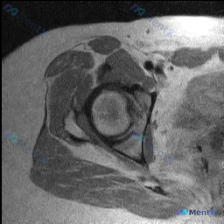

整理了一个髋关节MRI病例,先只放T2冠状位的影像分析。 核心信息: - 右侧髋关节MRI(T2冠状位) - 股骨头内侧近关节面下骨髓区:边界欠清的斑片状低信号影 - 关节间隙、髋臼、周围软组织无明显异常 用户最初问题是“盂唇病变”,但影像的核心发现是骨内异常信号。 大家第一眼看到这个低信号,会优先...

最近整理到一个髋关节MRI影像分析的病例,患者临床怀疑盂唇病变,但提供的单张T1轴位片未显示明确异常。报告详细分析了解剖结构、病变可能性、诊断路径等内容,其中有几个点比较值得讨论: 1. 单张T1轴位片对盂唇病变的敏感性如何? 2. 影像阴性但临床高度怀疑时,下一步应如何评估? 3. 盂唇病变的诊断...

整理了一个肩关节MRI轴位T1序列的病例资料,用户关心盂唇病变,但影像分析结果显示: - 盂唇形态完整,呈均匀低信号,未见明确撕裂征象 - 影像科指出单一T1序列对细微病变不敏感,建议补充PDFS序列、斜冠状位/斜矢状位 现在有几个问题想和大家讨论: 1. 单一轴位T1序列MRI对盂唇病变的评估局限...

看到一个髋关节MRI病例,单幅冠状位T2加权像显示髋臼外上缘盂唇有局灶性高信号改变。正常情况下,盂唇在T2加权像上应该是低信号的。大家看看这个高信号更可能是盂唇撕裂还是退变?还需要补充哪些序列的图像来明确诊断?

看到一份髋关节MRI分析材料,患者临床怀疑盂唇病变,但单幅冠状位T2序列显示: - 髋关节解剖结构完整,骨髓信号均匀 - 关节间隙清晰,软骨轮廓连续 - 髋臼盂唇未见明显形态异常或高信号撕裂影 - 关节周围软组织无明显水肿、萎缩或积液 这种影像阴性但临床高度怀疑的矛盾,大家怎么看?单张T2像能完全排...